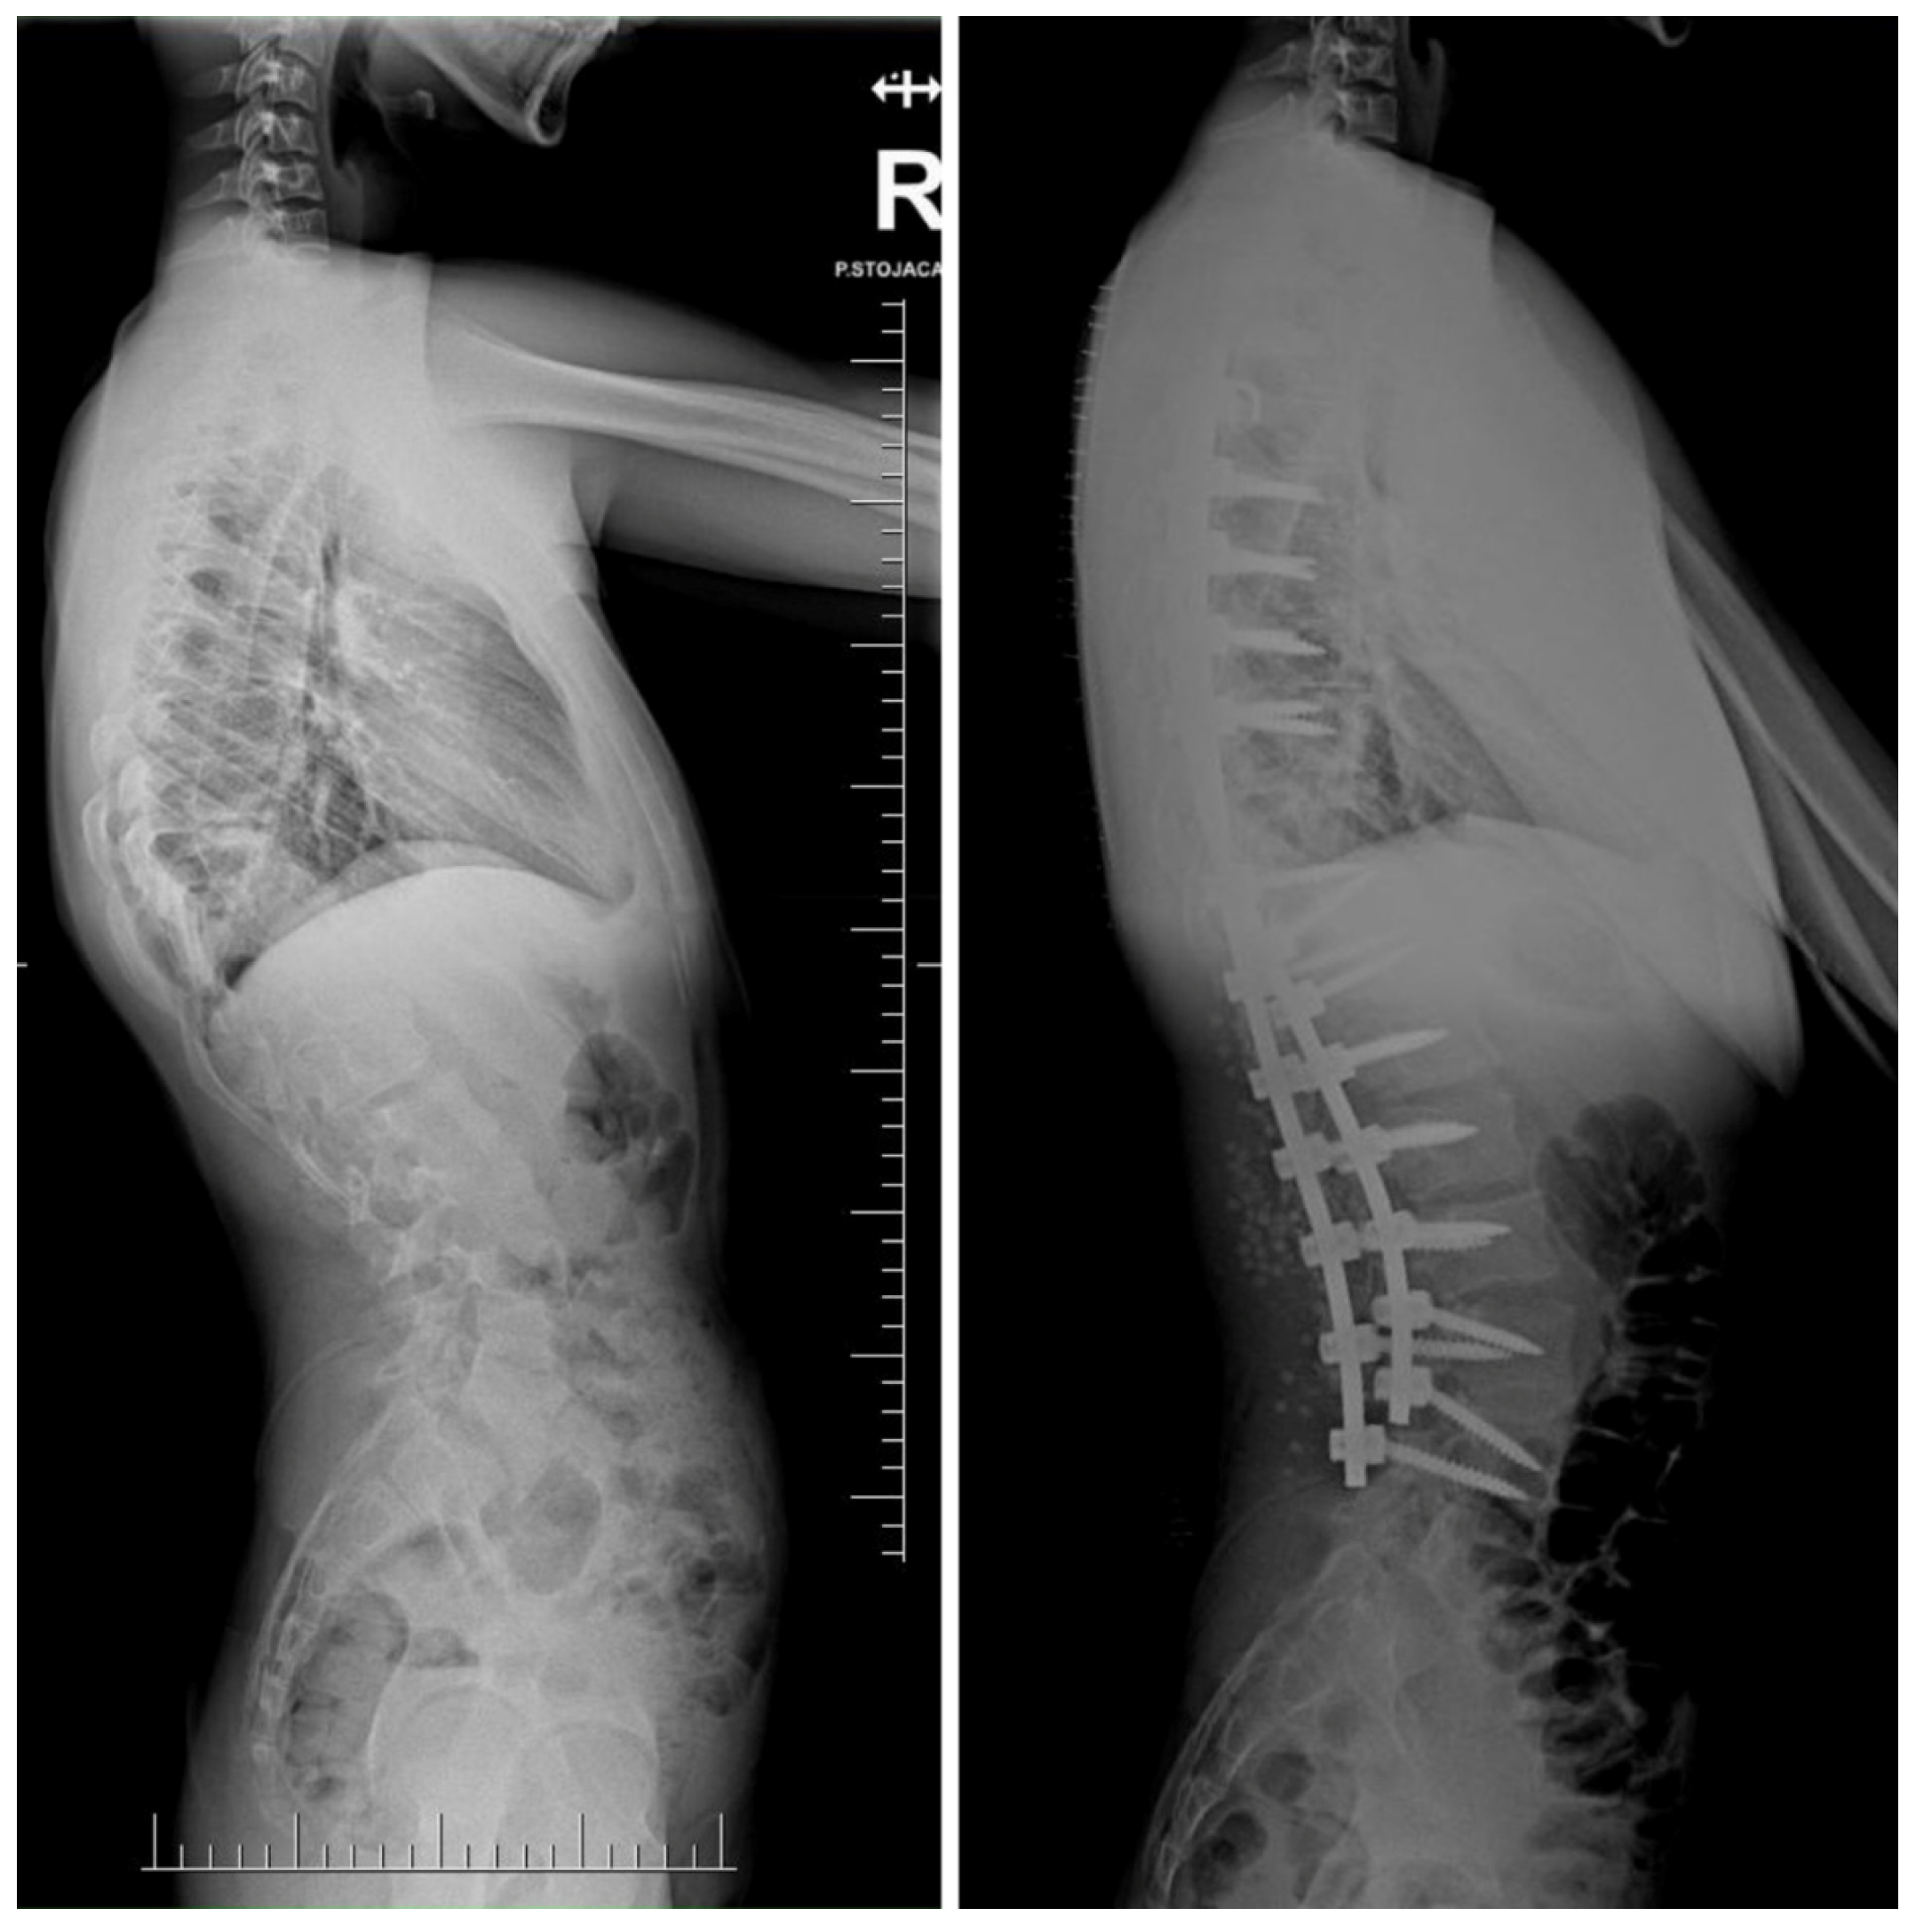

- Suk, S.I.; Chung, E.R.; Kim, J.H.; Kim, S.S.; Lee, J.S.; Choi, W.K. Posterior vertebral column resection for severe rigid scoliosis. Spine 2005, 30, 1682–1687. [Google Scholar] [CrossRef] [PubMed]

- Suk, S.I.; Kim, J.H.; Kim, W.J.; Lee, S.M.; Chung, E.R.; Nah, K.H. Posterior vertebral column resection for severe spinal deformities. Spine 2002, 27, 2374–2382. [Google Scholar] [CrossRef] [PubMed]

- Grabala, P.; Fani, N.; Gregorczyk, J.; Grabala, M. Posterior-only T11 vertebral column resection for pediatric congenital kyphosis surgical correction. Medicina 2024, 60, 897. [Google Scholar] [CrossRef] [PubMed]

- Asunis, E.; Cini, C.; Martikos, K.; Vommaro, F.; Evangelisti, G.; Griffoni, C.; Gasbarrini, A. Efficacy and Risks of Posterior Vertebral Column Resection in the Treatment of Severe Pediatric Spinal Deformities: A Case Series. J. Clin. Med. 2025, 14, 374. [Google Scholar] [CrossRef]

- Song, Z.; Zhang, Z.; Yang, X.; Zhao, Z.; Li, T.; Bi, N.; Xie, J.; Wang, Y. Posterior Vertebral Column Resection for Severe Spinal Deformity Correction: Comparison of Pediatric, Adolescent, and Adult Groups. Comput. Intell. Neurosci. 2022, 2022, 5730856. [Google Scholar] [CrossRef]

- Karami, M.; Zandi, R.; Hassani, M.; Elsebaie, H.B. Thoracolumbar and Lumbar Posterior Vertebral Resection for the Treatment of Rigid Congenital Spinal Deformities in Pediatric Patients: A Long-Term Follow-up Study. World Neurosurg. X 2022, 16, 100130. [Google Scholar] [CrossRef]